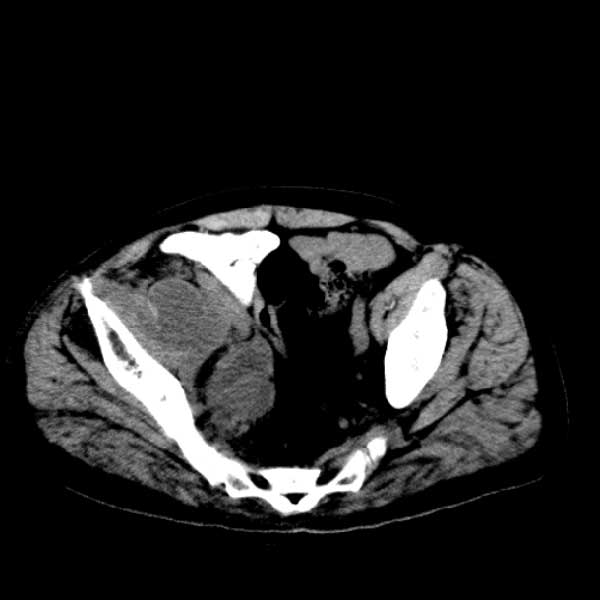

标题: CT13513:男 71 腹部疼痛20余天,近几天高热就诊,骨窗未见异 [打印本页]

标题: CT13513:男 71 腹部疼痛20余天,近几天高热就诊,骨窗未见异

考虑感染性病变可能性大,起源于阑尾?

感染,脓肿形成

考虑为化脓性阑尾炎.脓肿形成.及多肌肉累及.

考虑右侧腰大肌脓肿,向右髂窝、右腹股沟流注。

支持化脓性阑尾炎伴右髂窝脓肿、腰大肌腰方肌脓肿形成。

考虑腹腔及盆腔化脓性炎症,累及右侧髋关节及腹股沟区.

首先考虑化脓性阑尾炎伴腰大肌、腰方肌脓肿,不除外回盲部结核。

回盲部癌待排除。

患者肠镜检查考虑结肠癌,病理证实

患者肠镜检查考虑结肠癌,病理证实。肺部ct可见多发结节,考虑转移